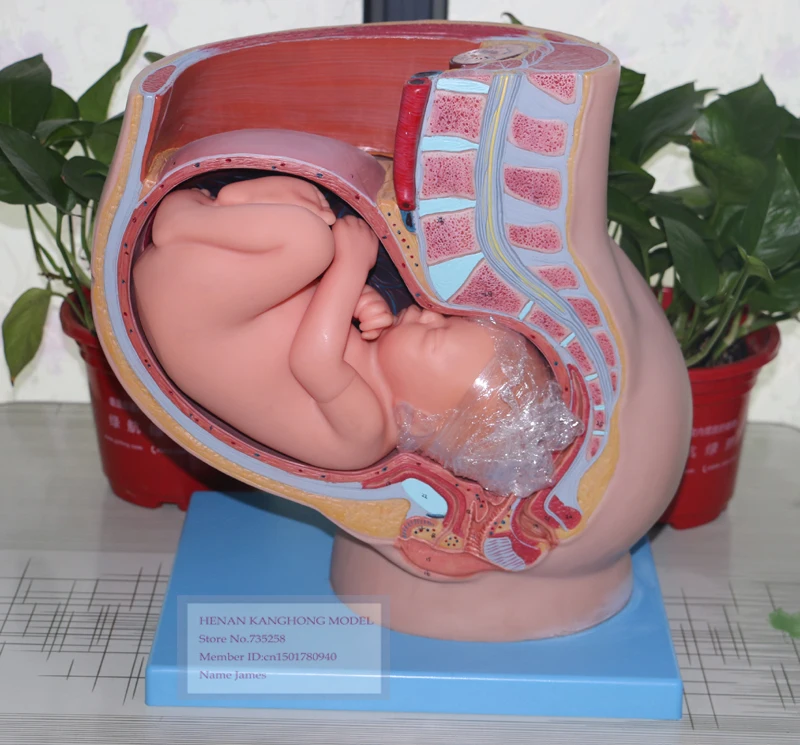

Удивительные моменты девятого месяца беременности на фотографиях

Раздел: Снимки-откровения